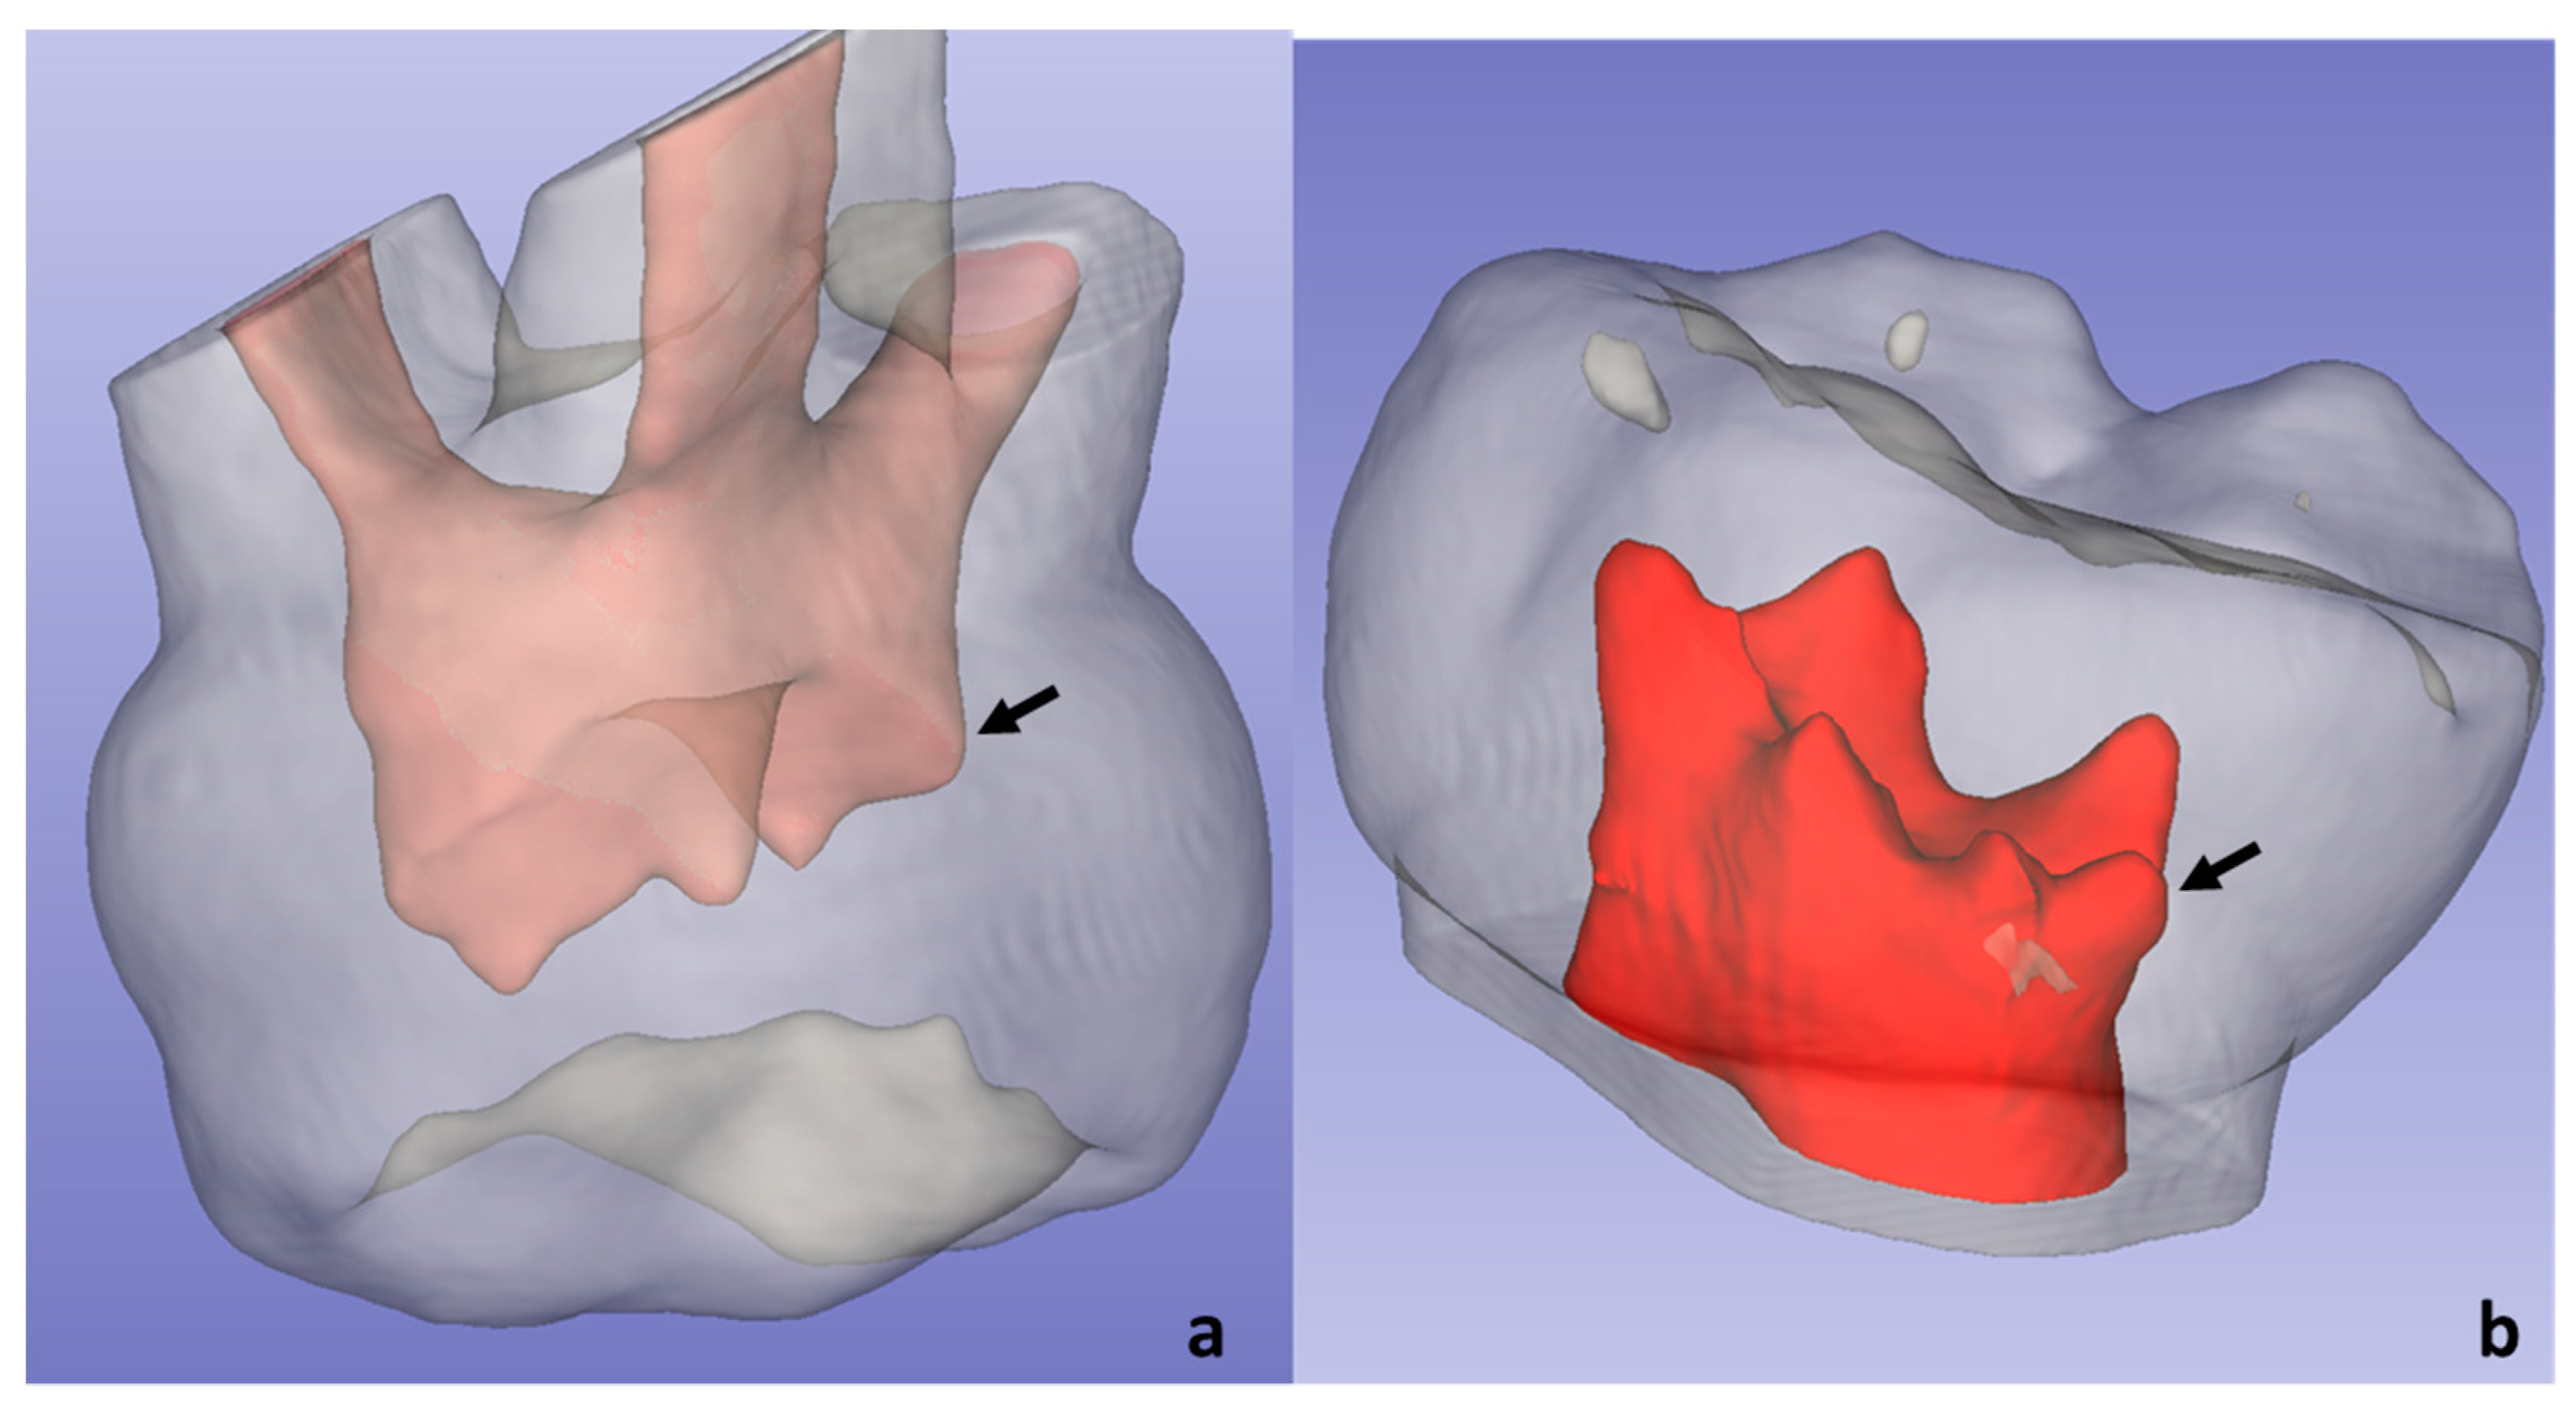

2.4.4. Other Peculiarities

4.5. Anatomical Peculiarities